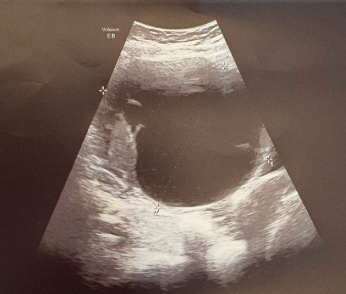

Realizamos ecografía abdominal clínica donde apreciamos en zona referida imagen quística, de contenido mixto de 11 centímetros, sin poder precisar si depende de útero u ovarios. Resto sin alteraciones reseñables. Derivamos a hospital de referencia para completar estudio.

En hospital de referencia, se realizan ecografía vaginal observando imagen quística en ovario izquierdo de gran tamaño.